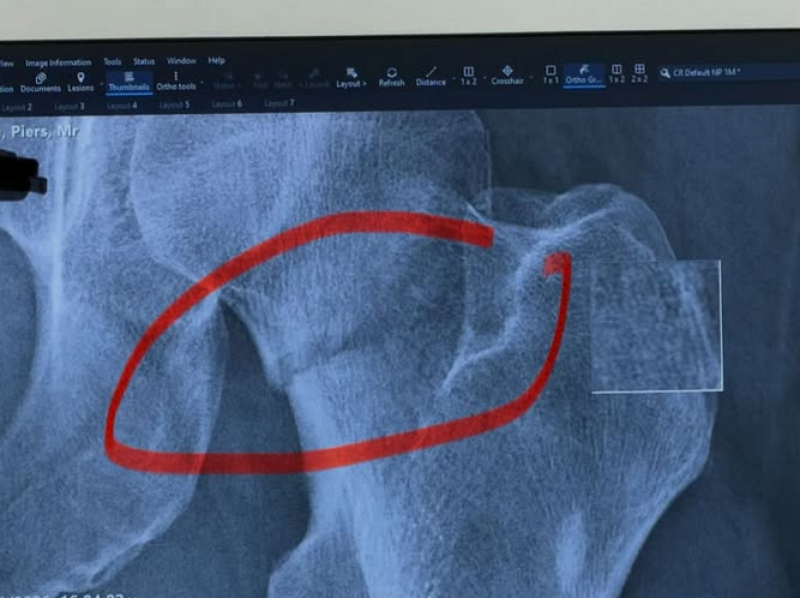

ทำแฟนๆต่างส่งกำลังใจให้อย่างมากสำหรับ เพียร์ส มอร์แกน พิธีกรชื่อดังวัย 60 ปี หลังเจ้าตัวถูกหามส่งโรงพยาบาลเป็นการด่วน จากอุบัติเหตุสะดุดล้มภายในร้านอาหาร จนกระดูกสะโพกหักจนต้องเข้ารับการผ่าตัดเปลี่ยนข้อสะโพกเทียม

แพทย์วินิจฉัยว่าอาการบาดเจ็บรุนแรงถึงขั้นต้อง ผ่าตัดเปลี่ยนข้อสะโพกใหม่ทั้งหมด พิธีกรระบุไทม์ไลน์การรักษาตัวว่า เขาต้องใช้ไม้ค้ำยันช่วยเดินเป็นเวลาอย่างน้อย 6 สัปดาห์ แพทย์ห้ามเดินทางไกลด้วยเครื่องบิน นานถึง 12 สัปดาห์ในช่วงพักฟื้น